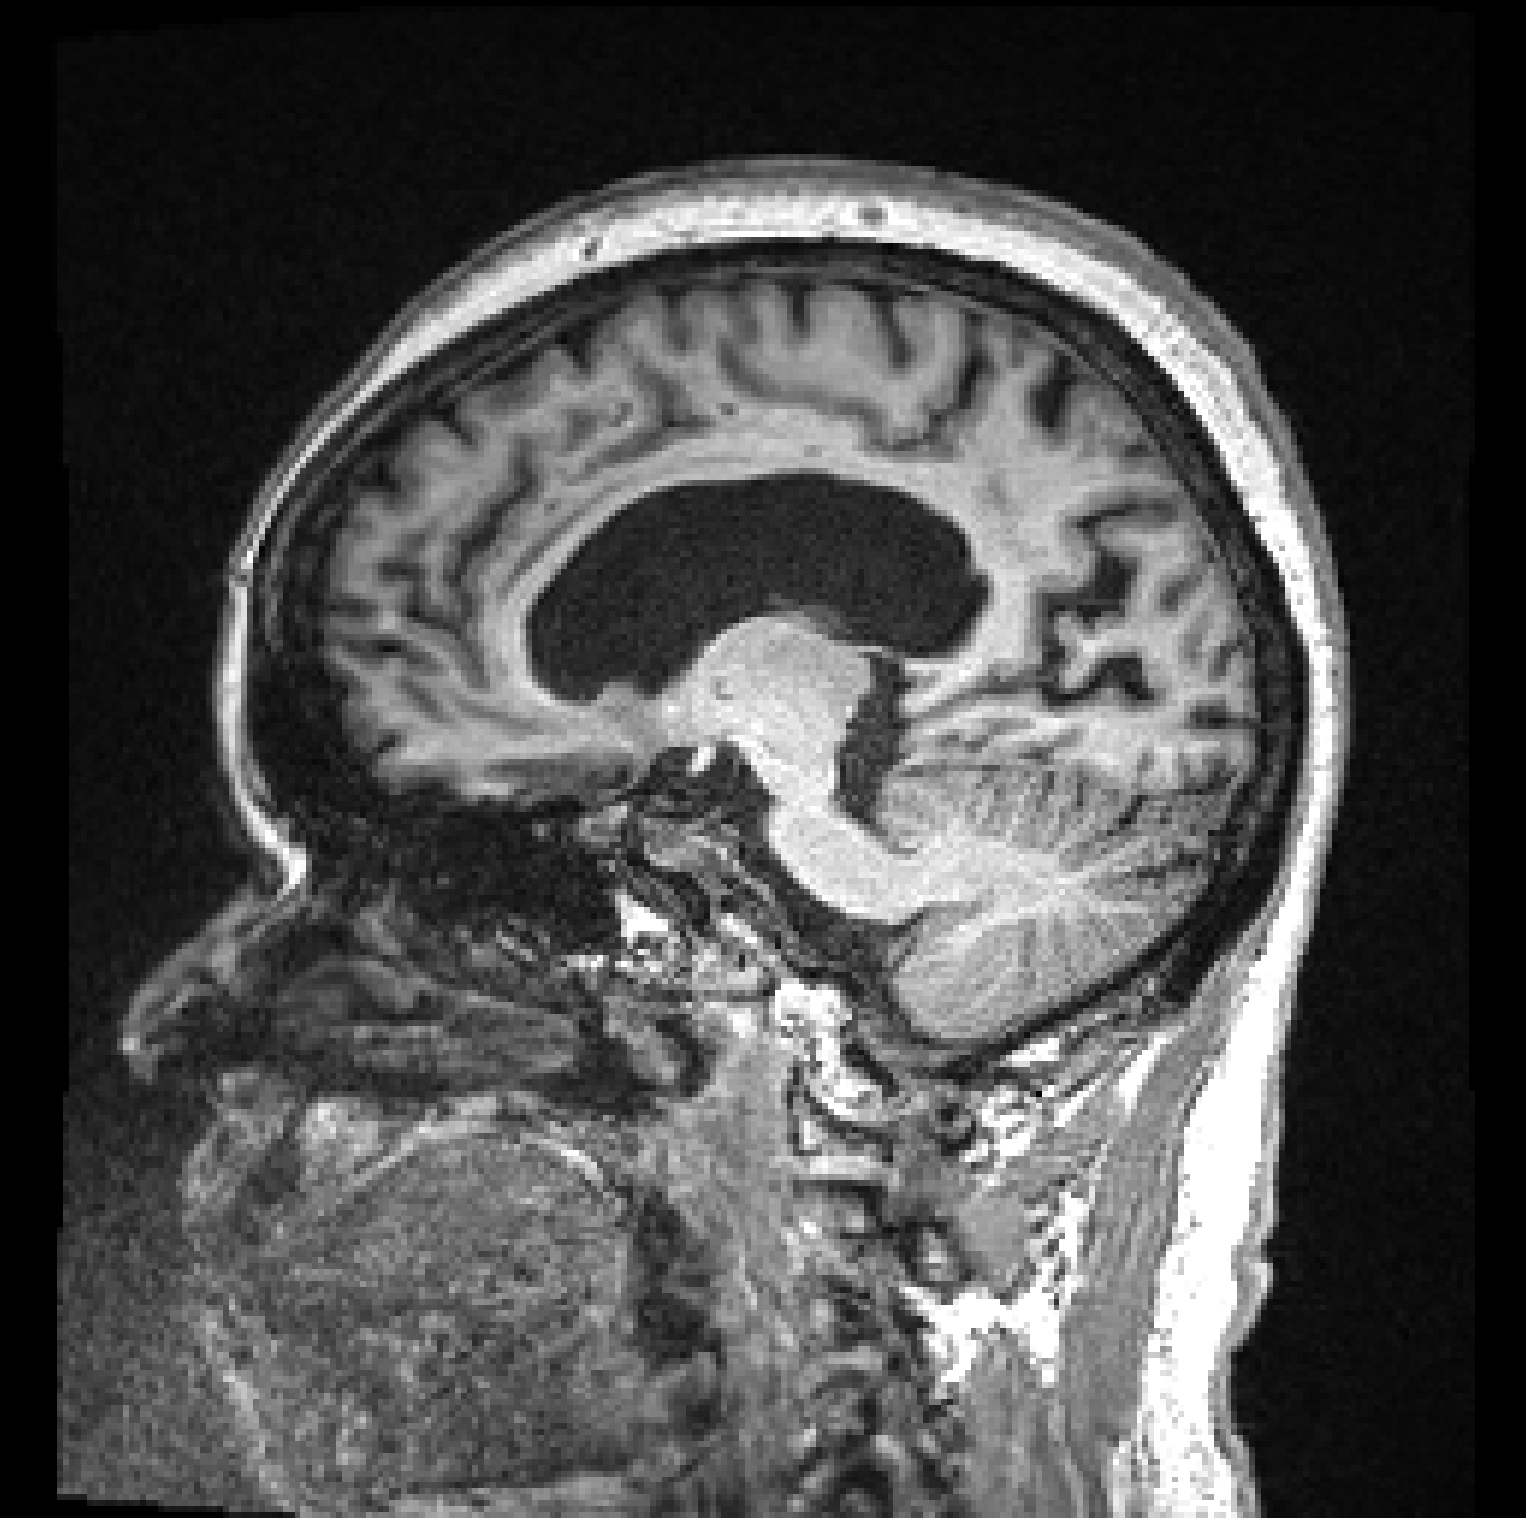

![]() |

| (a) | (b) |

Figure 1, presents two T1 images from the ADNI (Alzheimer’s Disease Neuroimaging Initiative) database, illustrating this difference. Both images, graded by trained analysts, have been deemed “unusable” for containing artefacts due to motion (the criteria used for the QC is described in detail on the ADNI website111http://adni.loni.usc.edu/methods/mri-tool/mri-analysis/). However, since in the right image the artefacts do not intersect the brain, the task of segmenting gray matter would not be affected and the scan should have been kept for this analysis. Thus, there is a distinction between perceptual quality and the quality required for algorithmic processing. Furthermore, by training with augmentation, convolutional neural networks (CNNs) make the internal representation of the data more robust to noise, so from an algorithmic perspective, some image degradation may be tolerated before observing a drop in performance. These observations allow us to define MRI quality as the model’s ability to perform the task, rather than a subjective visual grading of quality.